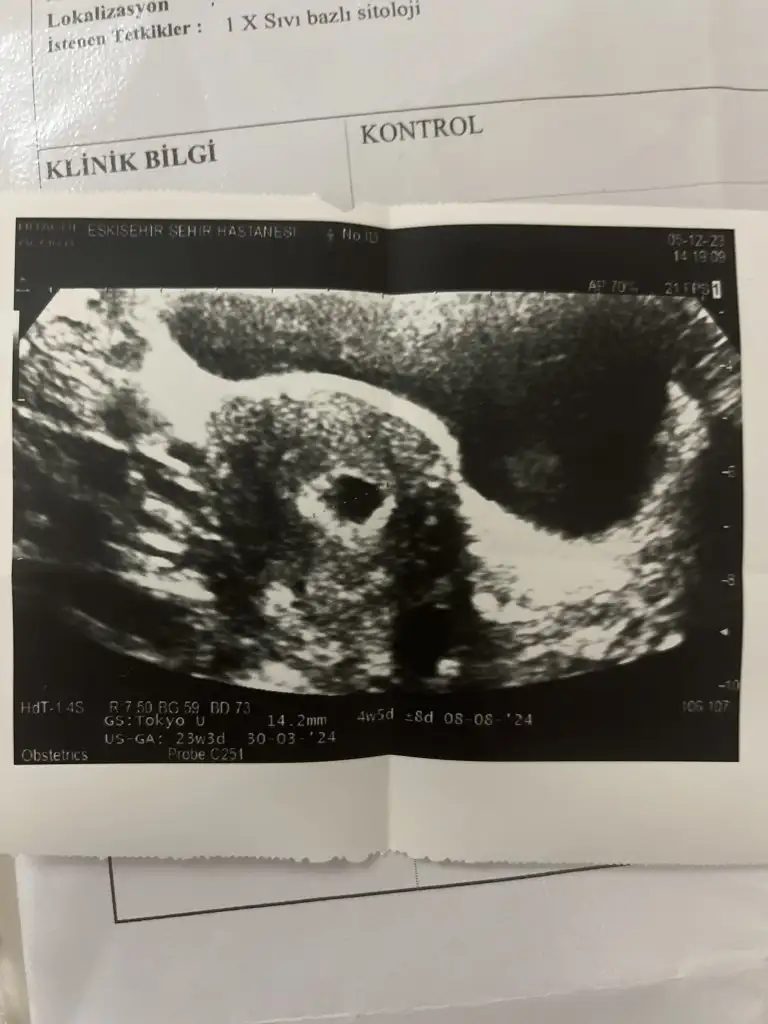

son adet 21 ekim muayene günü 5 aralık doktor muayenesinde herşey normal cıkmıştı. İlk ultrason görüntüsünü ve 26 aralıkta çekilmiş olanı koyacagım. Doktor gebeliğin sağlıksız genelik oldugunu söyledi. Kesede herhangi bir bebek yok ve kalp atısıda yok dedi. Bütün kan idrar değerlerim normal dedi. Yuvarlak baloncuk gibi gorunen lezyonlar olduğunu söyledi ve kürtaj ıcin 2 ocak a gün verdi. Ama doktor da garip dedi anlamadı ve bende ne plduğunu neden olduğunu asla anlamadım. Kese de gelısmemiş 20 gündür dedi cok üzgünüm dünden beri aglıyorum

Kesenin içinde yolc sac gordum yolc sac varsa genelde saglıklı gebelik olusuyor sizde gelişimi durmuş demekki. Sağlıklı gebelik olsaydı devam ederdi dogal bir secilim bu. Şuan devam etseymis 9 haftalık kocaman bir bebek olurdu.